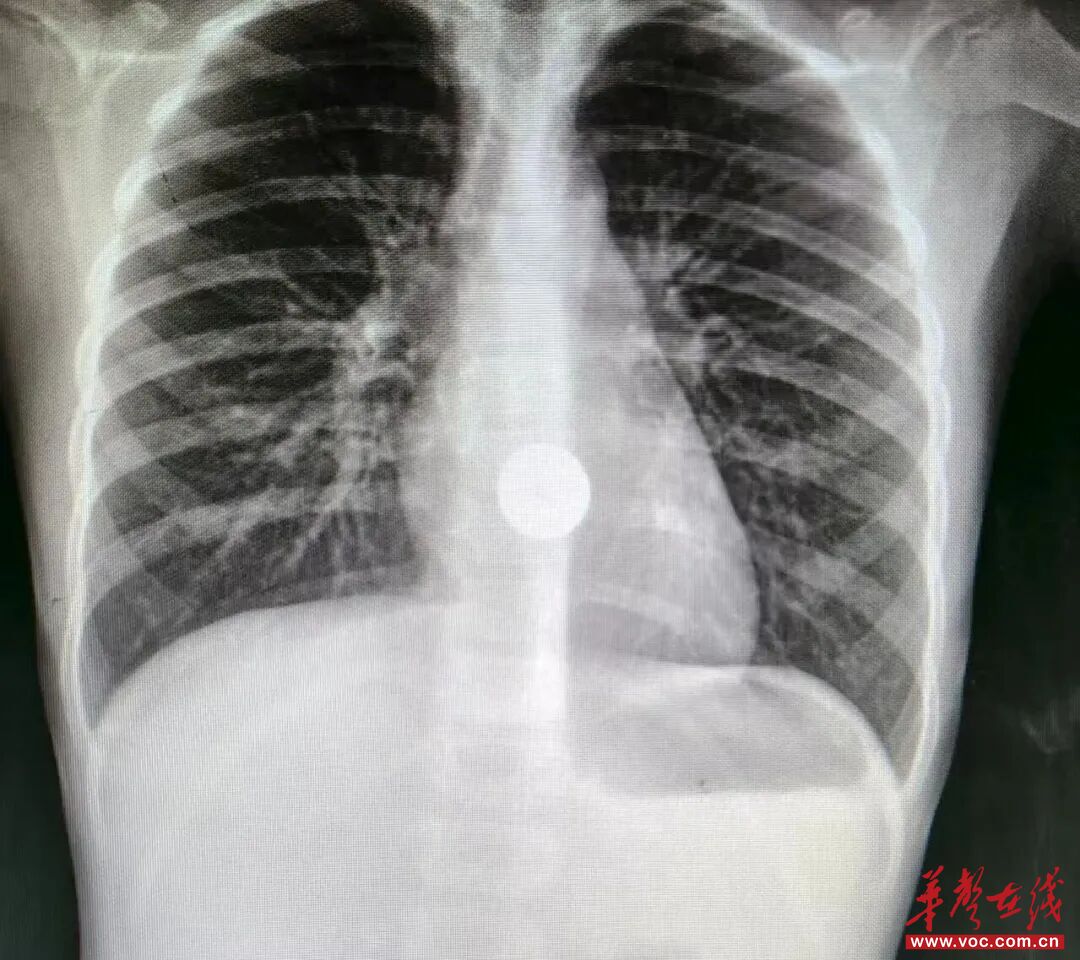

X光片中显示的硬币位置

检查X光片清晰地显示:一枚圆形金属异物正卡在朵朵的食管上段,紧邻气管入口。时间一分一秒过去,朵朵吞咽困难、流口水、胸口疼痛的症状越来越明显。消化内科副主任、主任医师谭智迅速做出判断:硬币位置危险,必须尽快取出。